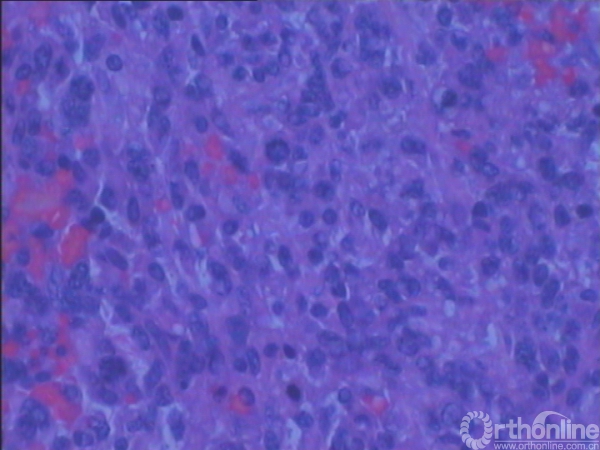

3.辅助检查:化验检查未见明显异常。B超显示右肘关节后方软组织内可见实性杂乱回声包块,1.5cm×1.0cm,界欠清,其内回声不均,可见少许血流信号。手术切口上端深处紧贴尺骨可见低回声小包块,0.9cm×0.2cm,未见血流信号。MRI(图2)示右肘关节后方皮下组织内可见软组织肿块影,边界不甚清楚,T1加权像呈现低信号,T2加权像呈中高信号,增强后T1加权像呈高信号,抑脂像亦呈现高信号。会诊病理(图3)显示成片较密集的轻度-中度间变的短梭形细胞,纤维性间质局部粘液变。初步考虑梭形细胞肉瘤Ⅱ级,可符合恶性外周神经鞘瘤形态。

图3:病理组织学镜下像(×200,H-E染色)